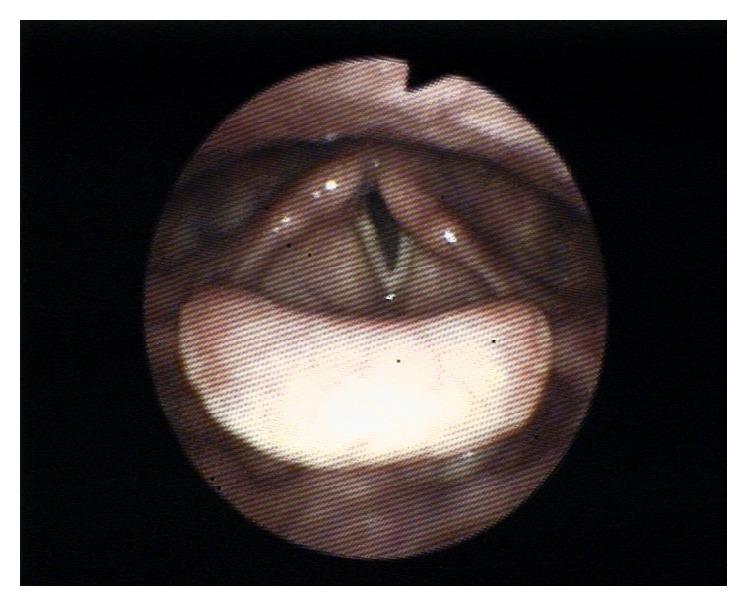

Since its introduction in 1988 by Dr. Archie Brain, the laryngeal mask airway (LMA) is being used with increasing frequency. Its ease of use has made it a very popular device in airway management and compared to endotracheal intubation it is less invasive. The use of LMA was on the rise, so has been the incidence of its related complications. We report severe unilateral vocal cord paralysis following the use of the supreme laryngeal mask (sLMA) in a patient with syndrome. In addition, we propose possible mechanisms of injury, review the existing case reports, and discuss our findings.

自1988年阿奇·布雷恩博士引入喉罩气道(LMA)以来,其使用频率日益增加。其使用便捷性使其成为气道管理中非常受欢迎的设备,与气管插管相比,侵入性较小。LMA的使用呈上升趋势,其相关并发症的发生率也随之上升。我们报告了一名患有[具体综合征名称未给出]综合征的患者在使用高级喉罩(sLMA)后出现严重单侧声带麻痹的情况。此外,我们提出了可能的损伤机制,回顾了现有的病例报告,并讨论了我们的发现。